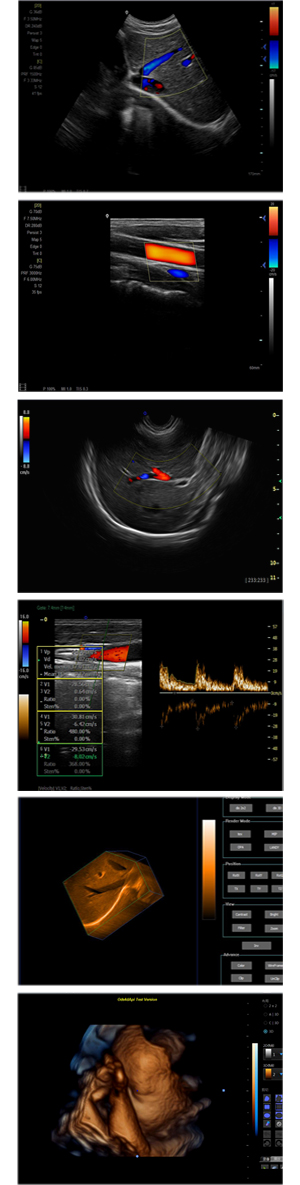

XF-7800型,秉承先鋒彩超技術(shù)之精華,擁有高雅大氣的獨(dú)特外型,為最新一代應(yīng)用型數(shù)字彩色多普勒診斷系統(tǒng),魅力與實(shí)力相融合??蓮V泛適用于腹部、婦產(chǎn)科、心臟、小器官、乳腺、肌骨及外周血管等諸多方面的診查,讓您在臨床超聲診斷應(yīng)用領(lǐng)域得心應(yīng)手,綻放異彩!

突破的成像技術(shù)

● 3D/ 4D成像技術(shù)/限7800選配

● 應(yīng)用于腹部、腎臟、泌尿系統(tǒng)、產(chǎn)科、婦科、盆腔、大動(dòng)脈、肌肉組織、小器官、乳腺、心臟等

● 能量多普勒成像(PDI)

● 彩色血流量圖(CDE)

● 脈沖頻譜多普勒成像(PW)